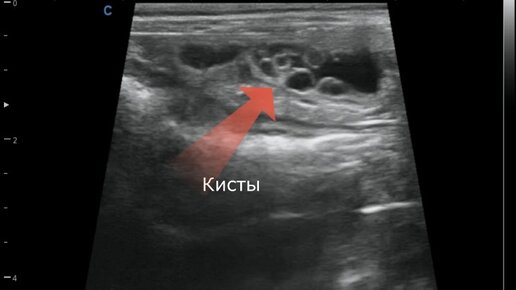

Ультразвуковые признаки кистозной гиперплазии эндометрия

Кистозная гиперплазия эндометрия - это патологическое разрастание слизистой оболочки (эндометрия) матки с преимущественным образование кист различного диаметра и утолщения стенки в целом. В основном диагностируется у самок пожилого возраста (старше 7 лет). Чаще всего это гормонозависимые изменения эндометрия. Основные причин возникновения данной патологии: - Отсутствие случки в течение всей жизни; - Дача препаратов для подавления признаков течки (например, секс барьер); - Во время не проведенная овариогистеректомия...